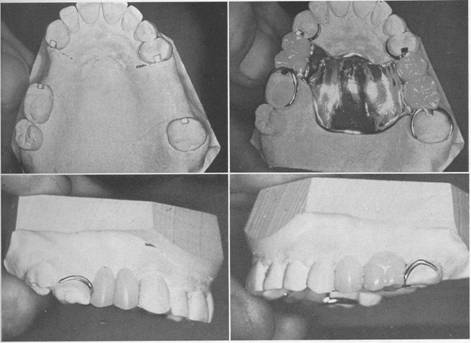

Fig. 6-1 A, Framework for tooth-supported removable partial denture. Arrows point to components (rests) located on specifically prepared areas Of abutment teeth. Denture will be supported through three occlusal rests and one incisal rest on canine. B, Canines have been restored with ceramic-metal crowns on which lingual rest seats have been developed to support a linguoplate major connector. C, Tooth support for this framework is provided by rests occupying definite, prepared, lingual rest seats on canines and occlusal surfaces of posterior teeth. D, Maxillary unilateral distal extension removable partial denture supported by rests occupying lingual rest seats on canines; mesio-occlusal rest seat on second premolar and distoclusal rest seat on first molar.

Fig. 6-13 Mandibular internal rest-supported partial denture. A, Abutment crowns with internal rests. Both dovetail design and gingival will prevent horizontal movement. H, Completed partial denture framework with cast lingual retention on all four abutments. Short buccal stabilizing arms on molar abutments facilitate removal of the partial denture.

Fig. 6-14 Mandibular internal rest partial denture. A, Internal rests in four abutment crowns. H, Occlusal view showing proximal guiding planes. C, Buccal view showing machined parallelism of proximal surface. D, Completed casting with wrought-wire lingual retention on all four abutments. Use of buccal stabilizing arm is optional.

Fig.6-15 Maxillary internal rest partial denture. A, Internal rest seats in four abutment crowns. B, Completed partial denture with lingual retentive clasp arms on canine and premolar abutments. C and D, Buccal views of completed restoration showing abutted improved resin teeth and absence of visible clasp arms on premolar abutments.